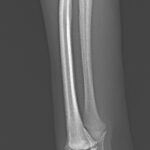

Toy Poodleさんがソファーより転落後に橈骨近位を斜骨折したとの事。1.5 Locking Plateで固定術を実施しました。 しばらく安静が必要です。